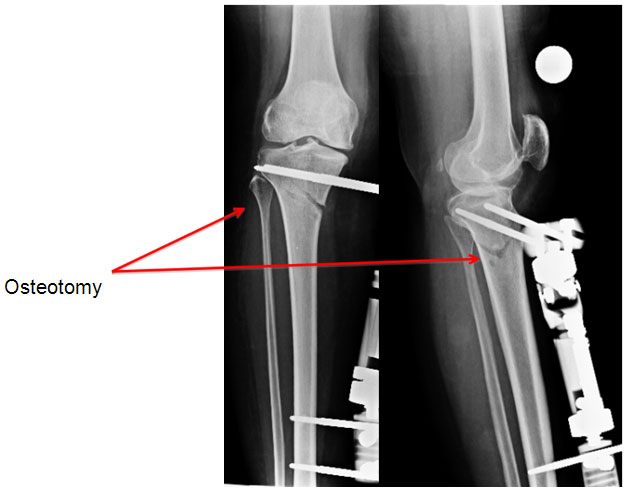

| Post Surgery |

| During the surgery the bone is cut (High Tibial Osteotomy) and the fixator is applied. |